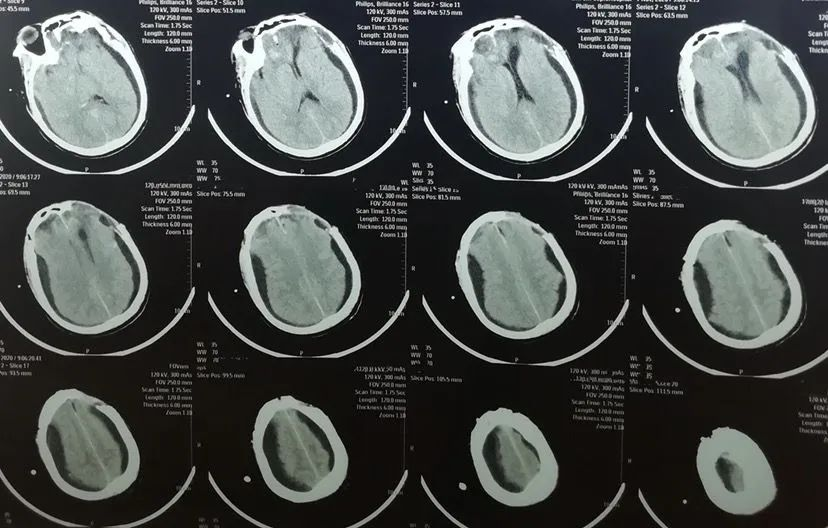

给予行左额颅骨成形术,术后双侧硬膜下积液消失,但出现脑积水,也就是脑外积水转为脑内积水。

早期颅骨修补术尽早恢复颅骨形态和颅腔完整性,使颅内压恢复平衡状态,对治疗去骨瓣减压术后硬膜下积液起到积极作用,可有效减少并发症,疗效令人满意。但有一部分患者由硬膜下积液(脑外积水)转为脑积水(脑内积水),仍需密切观察,必要时手术治疗。